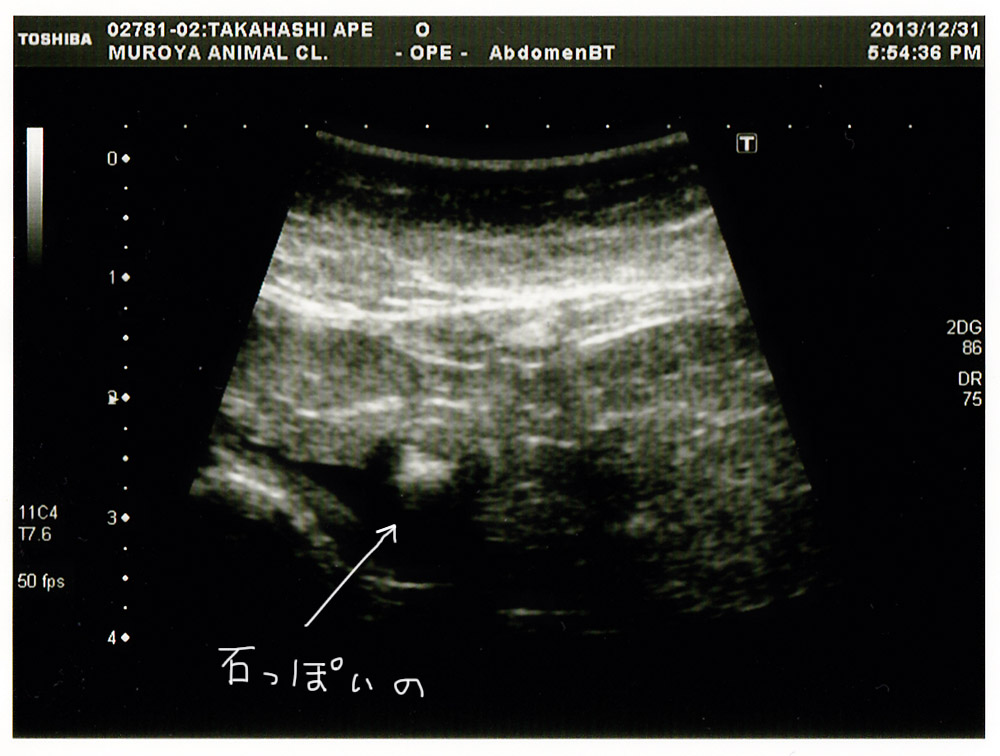

前回の膀胱の様子。

石っぽいものがあったけれど、今日エコー撮ったら

バラバラに溶けていました。